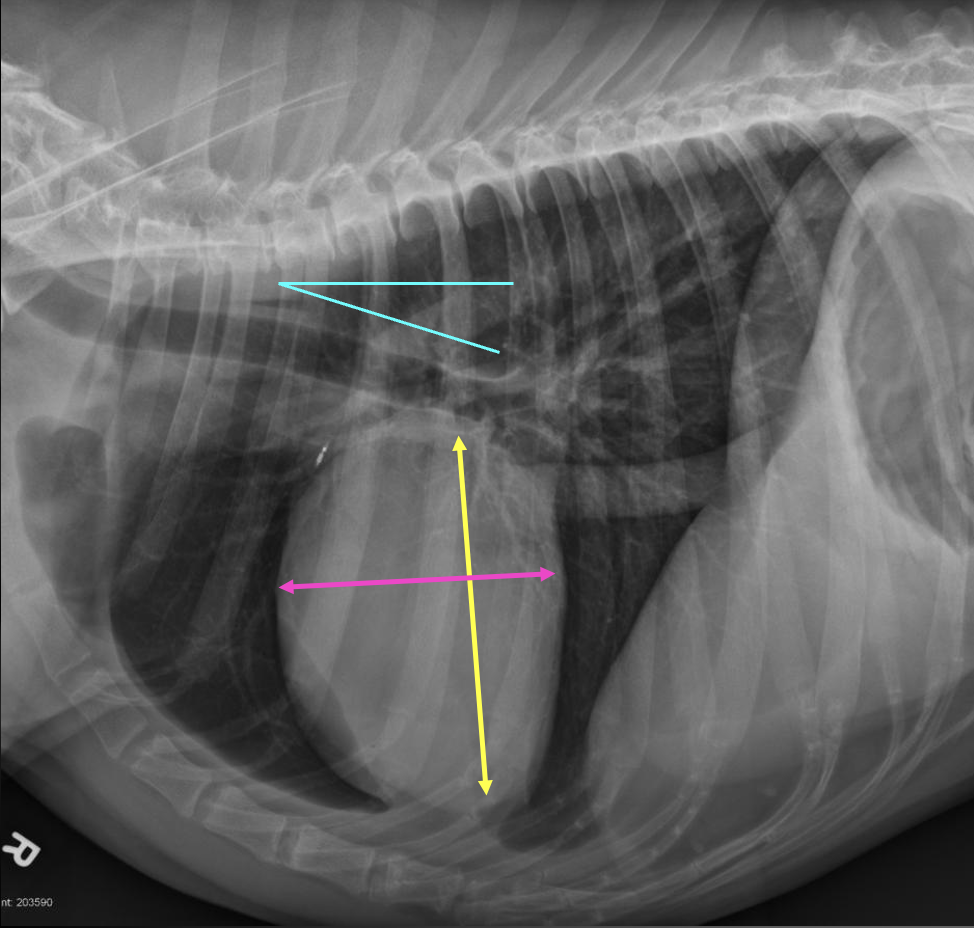

Q

What are the normal characteristics of the feline heart in a lateral view?

A

-heart height is ~ 2/3 of the diameter from dorsal to ventral chest (yellow)

-heart is 2 to 2.5 intercostal spaces wide (pink)

-trachea deviates from spine (blue)